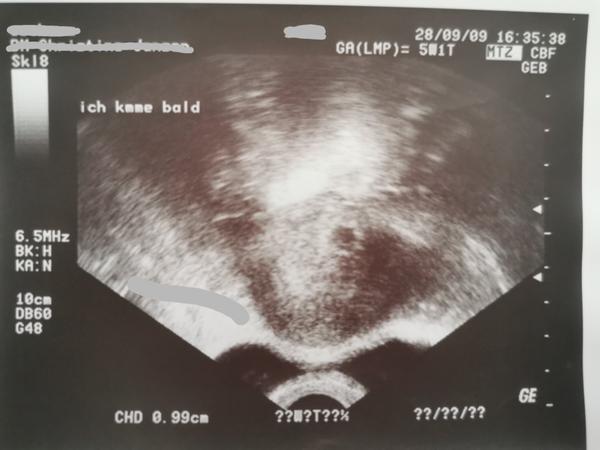

Prvú foto mám z 18.5.2020. Posledná menstruacia bola 28.3. Čiže len pár dní po vynechani menštruácie.

"Bábo" tam malo 7mm. Ja som bola u lekára veľmi skoro lebo sa mi menila liečba a pod. Strážili ma od úplného začiatku. Súkromná klinika. Pôrod bol v noci zo 17 na 18.12.2020, čiže presne 7 mesiacov od tejto fotky.